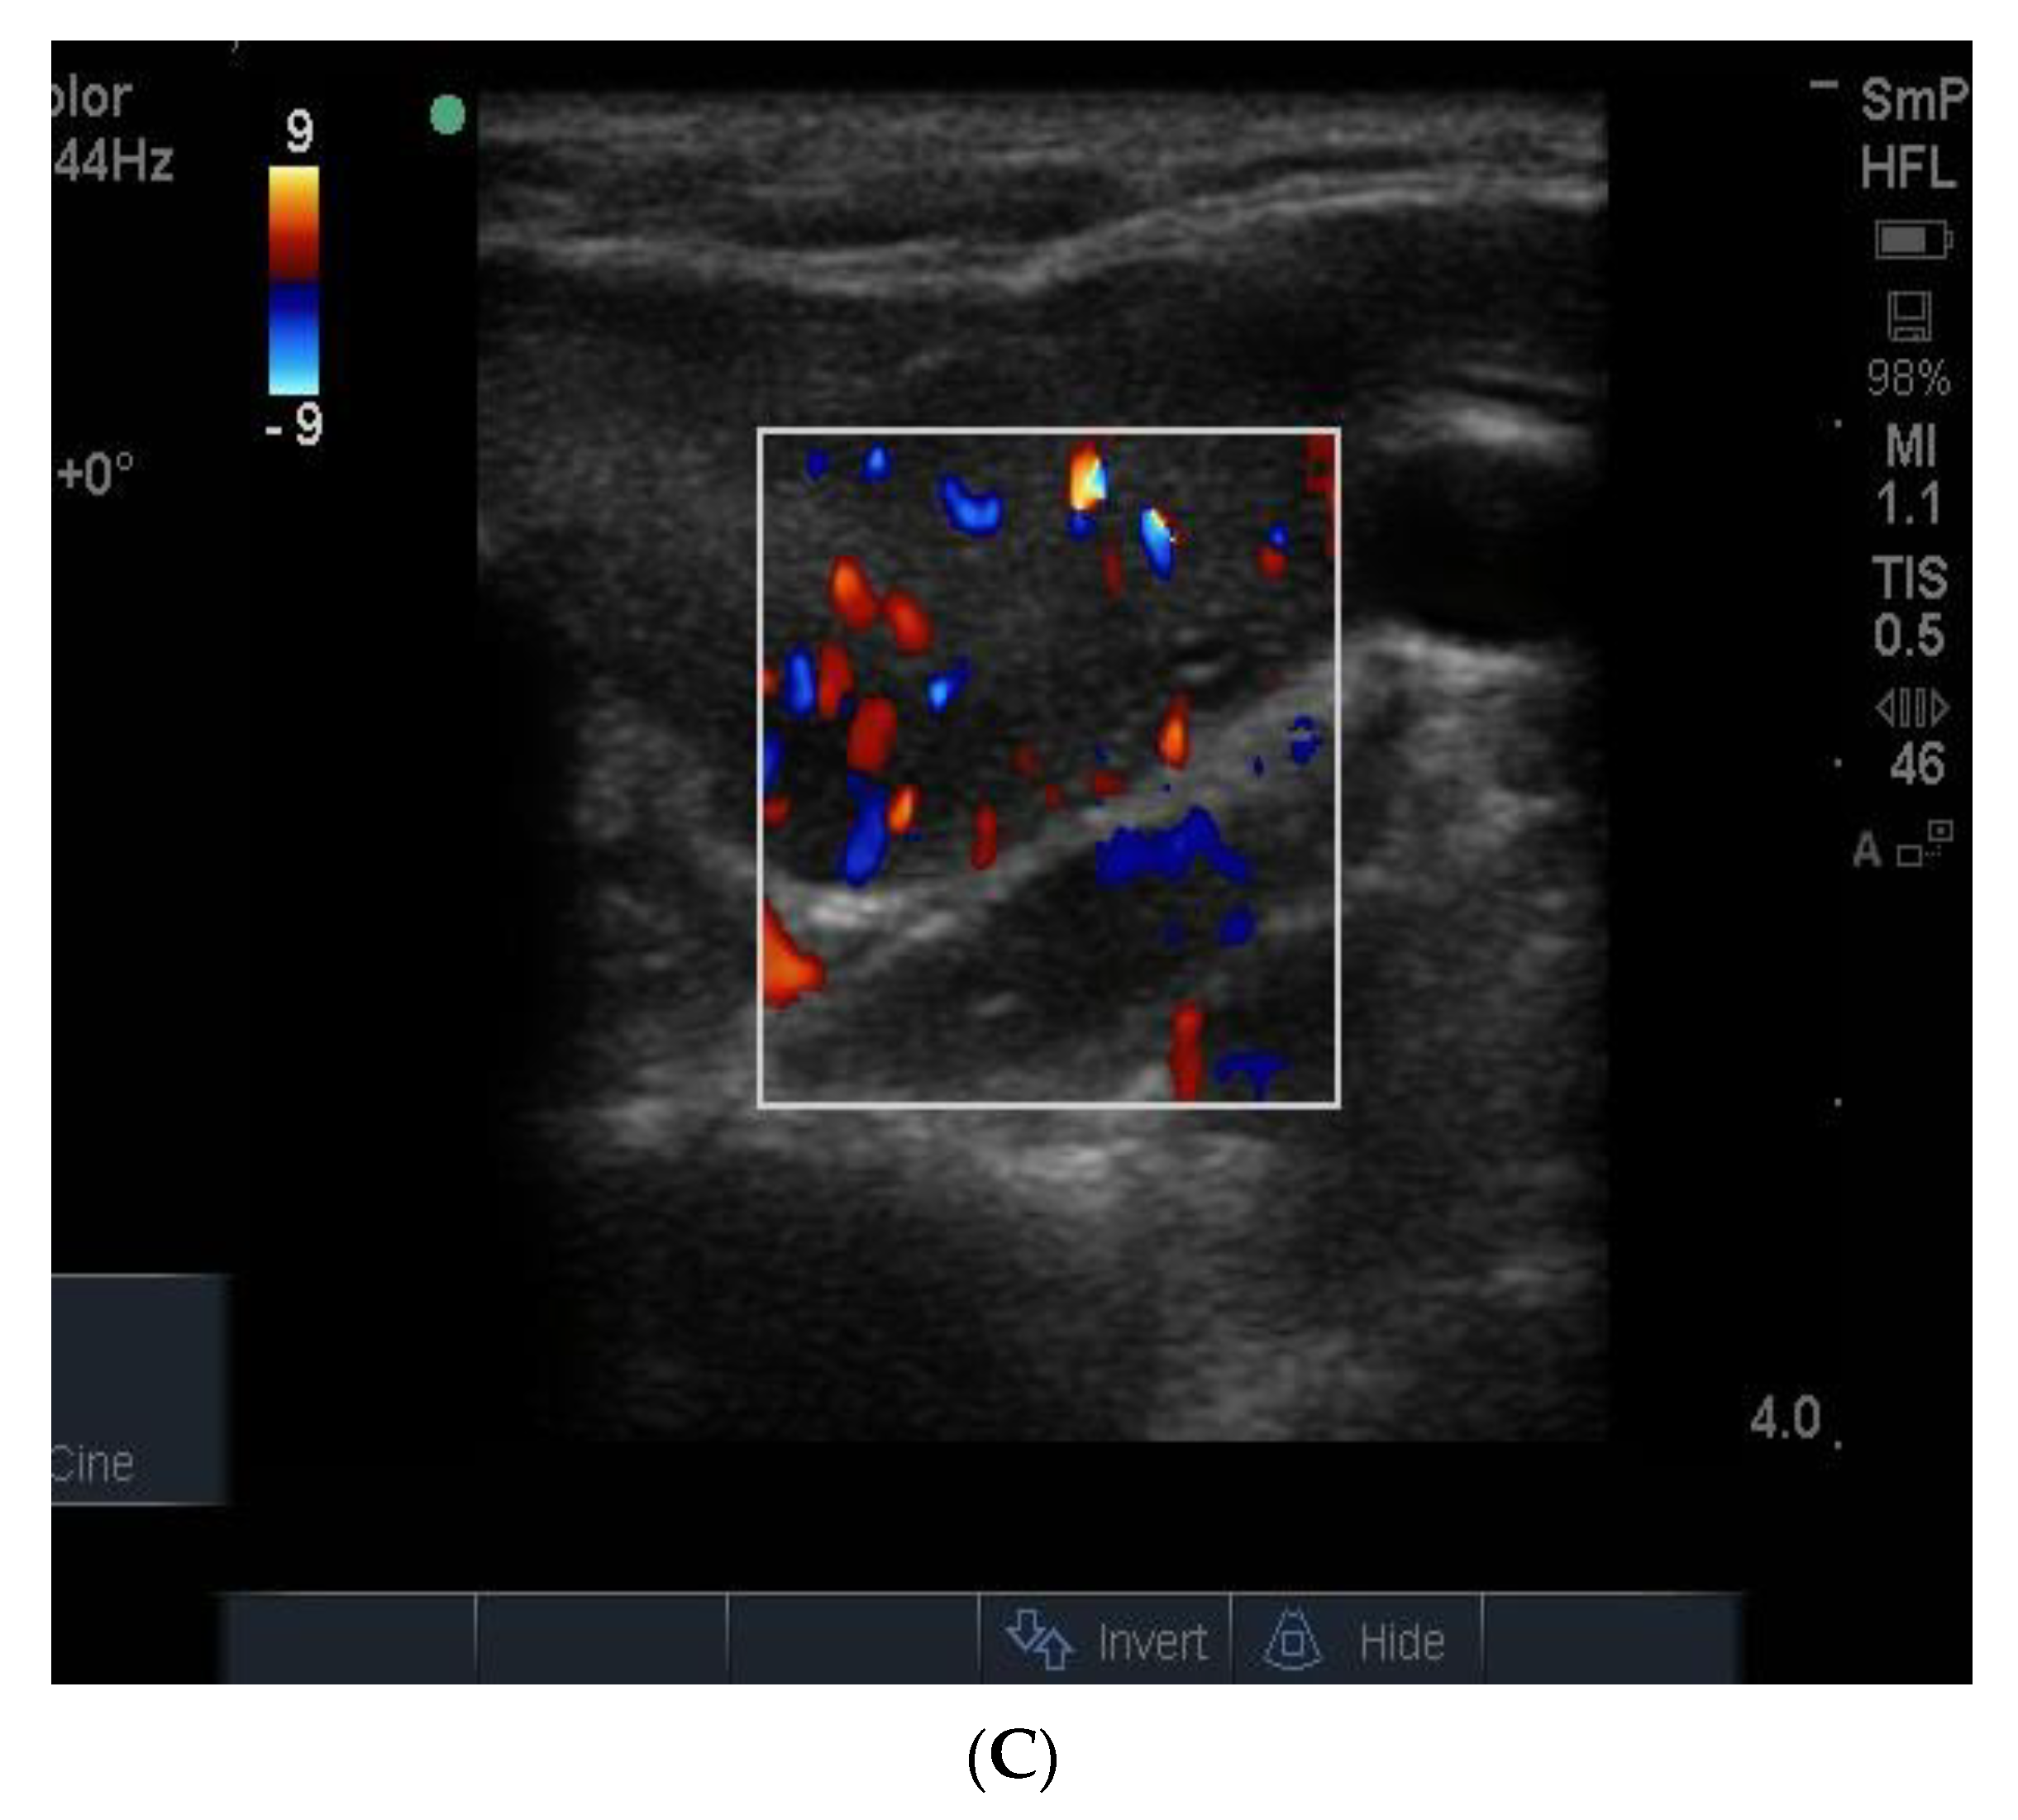

The blood supply in typical Graves’ disease is diffusely increased (and associated with a murmur), sometime up to 100 times normal, and the gland texture on ultrasound is usually heterogeneous (patchy) with a fine cystic appearance throughout, which reflects the diffuse nature of the inflammatory process (Figure 15). Following radio iodine treatment, the normal gland architecture is disrupted because the follicles are destroyed, and scar tissue predominates.

Figure 15.

Thyroid ultrasound from two patients with Graves’ hyperthyroidism. In (A) is shown an example of early Graves’ hyperthyroidism manifest as multiple small inflammatory and lymphoid lesions, often described by the consultant radiologist as “nodules” blue arrow. In (B) is shown an enlarged thyroid, with a thick isthmus and a generalized patchy hypo echoicity due to the lymphocytic inflammation and thyroid cell proliferation. In (C) is shown the increased vascularity in the thyroid of the patient shown in (B).